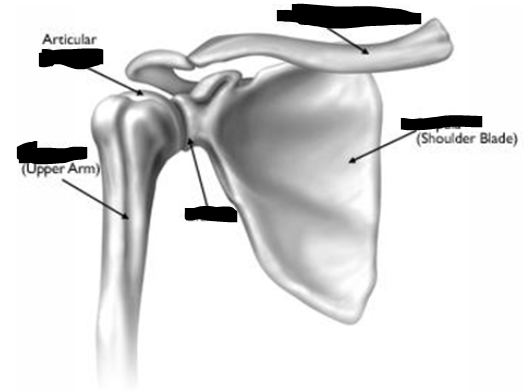

Normal Anatomy: Shoulder

A